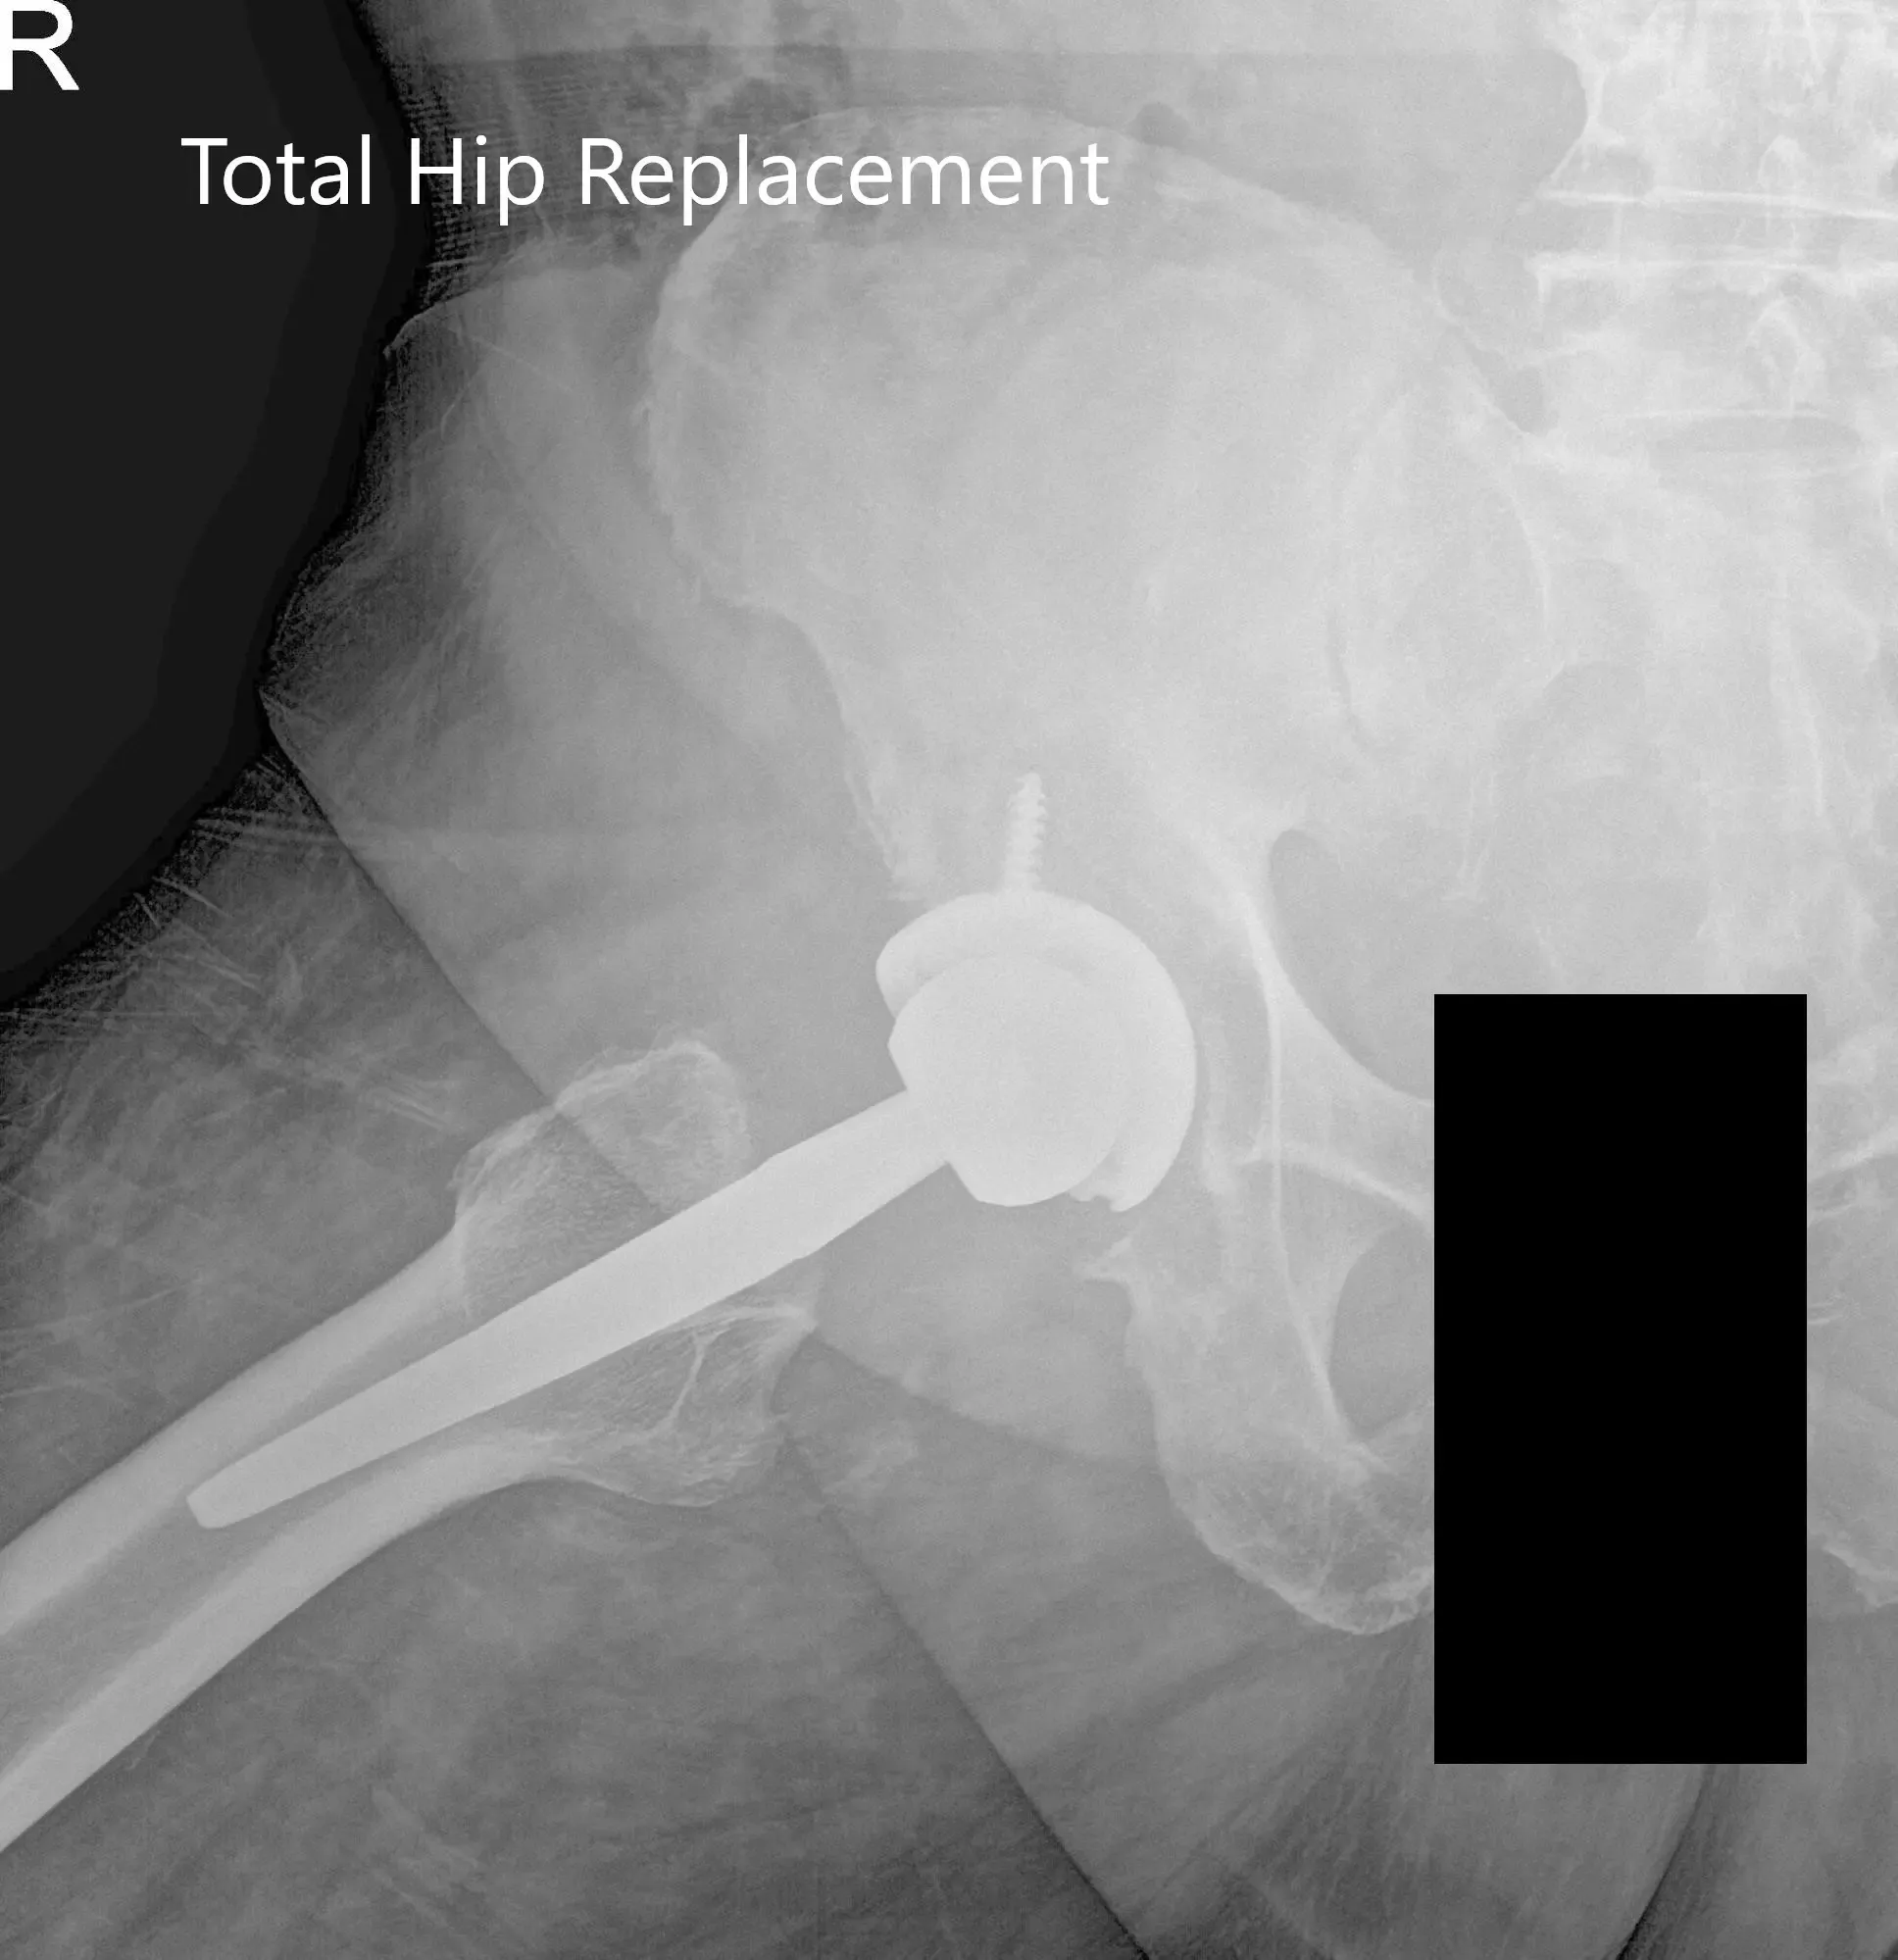

IMPLANTES UTILIZADOS: copa de 52 mm con tornillo de 6,5 mm, 25 mm de longitud con polietileno de 0 grados con tallo de 127 grados y cabeza femoral cerámica de 36 mm menos 2,5.

Radiografía postoperatoria que muestra vistas laterales de la cadera derecha y de la pata de rana